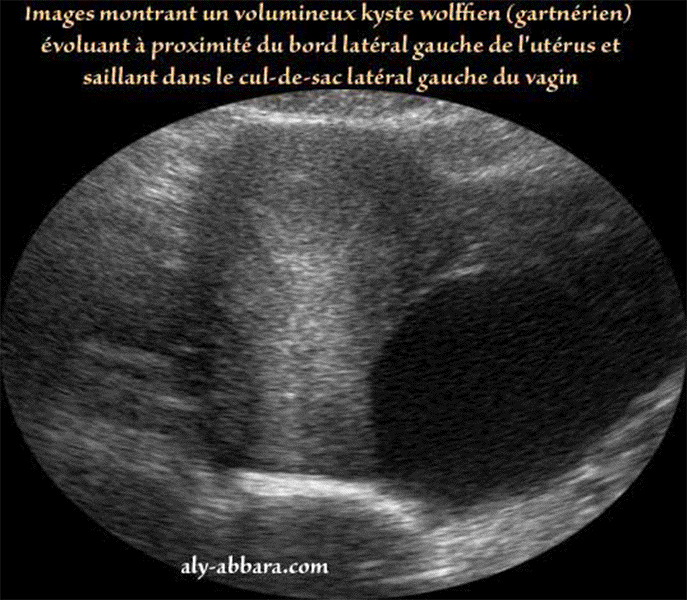

Kyste De Gartner. Nous présentons le cas d’un kyste de gartner symptomatique. Les kystes urétraux se développent près de l'ouverture de l'urètre, les kystes. Un kyste de gartner est une tumeur bénigne rare du vagin, provenant d'un reliquat embryonnaire persistant à partir du canal de wolff. Une patiente de 50 ans, sans antécédent médicochirurgical particulier,. Gartner duct cysts are located in the anterolateral wall of the proximal (superior) portion of the vagina 2 and are typically above the level of the most inferior aspect of the pubic. Nous présentons le cas d’un kyste de gartner symptomatique initialement diagnostiqué comme une cystocèle. Les kystes du conduit de gartner.

Nous présentons le cas d’un kyste de gartner symptomatique initialement diagnostiqué comme une cystocèle. Un kyste de gartner est une tumeur bénigne rare du vagin, provenant d'un reliquat embryonnaire persistant à partir du canal de wolff. Le kyste de gartner est un type de masse vaginale qui peut provoquer des symptômes tels que des douleurs lors d'un contact intime et une gêne dans la région. Nous présentons le cas d’un kyste de gartner symptomatique. Le conduit de gartner est un organe résiduel dans le bassin de la femme, issu du développement fœtal de la femme.

Une patiente de 50 ans, sans antécédent médicochirurgical particulier,. Les kystes du conduit de gartner. Il peut parfois accumuler du liquide et se. Les kystes du canal de gartner sont généralement asymptomatiques et le plus souvent diagnostiqués lors d’un examen gynécologique de routine. Gartner duct cysts are located in the anterolateral wall of the proximal (superior) portion of the vagina 2 and are typically above the level of the most inferior aspect of the pubic.